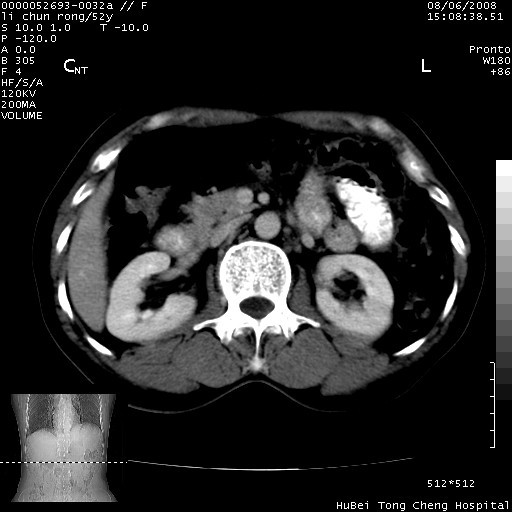

以下是引用云翔在2008-8-7 6:20:00的发言:[br]胰尾部囊性病变,考虑假囊肿,结合实验室检查疾病史

以下是引用zjzjr在2008-8-7 8:38:00的发言:[br]支持胰腺炎伴假囊肿形成,左肾小囊肿.少量腹水.

以下是引用随光逐影在2008-8-7 9:12:00的发言:[br]1)考虑胰腺炎伴假性囊肿形成可能性大;胰腺囊腺瘤待排。2)左肾小囊肿。3)少量腹水。